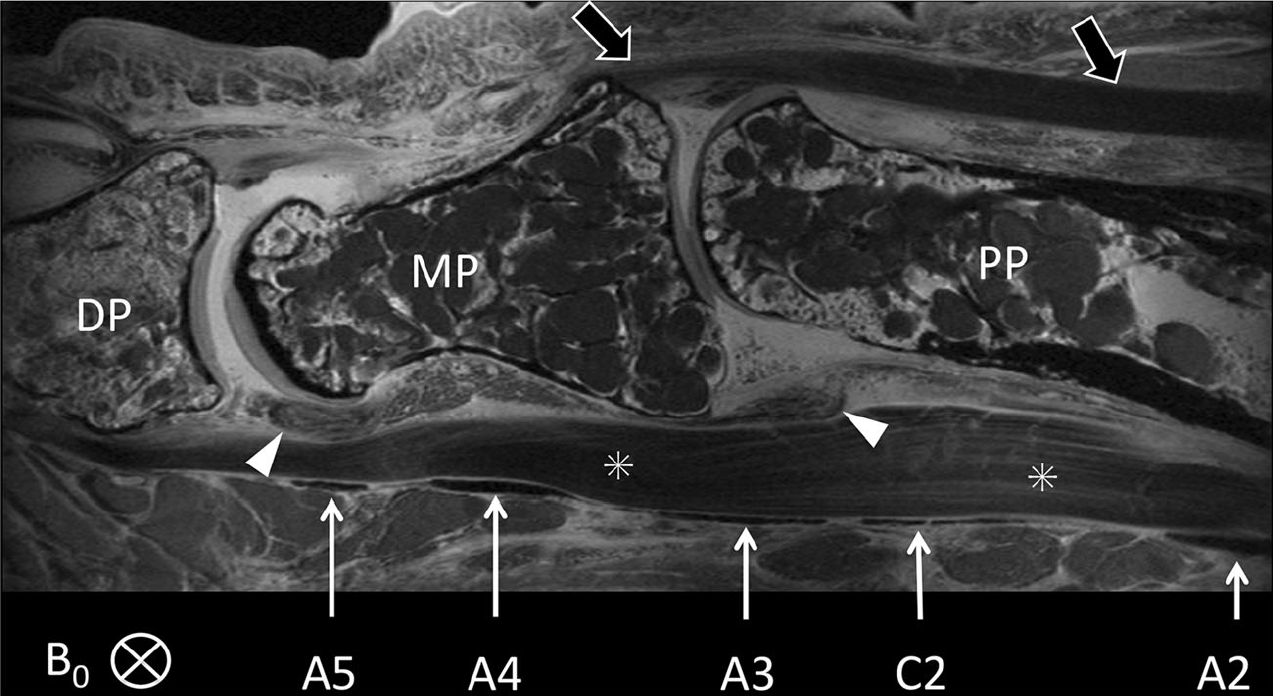

Sagittal fat-saturated SE scan (TR 3,500 ms/TE 15.7 ms) of the distal portion of the proximal phalanx (PP), the middle phalanx (MP) and the proximal portion of the distal phalanx (DP) of the 4th toe was obtained. The annular (A2, A3, A4, A5) and cruciate (C2) pulleys are seen in cross section as thin hypointense bands (arrows) superficial to the flexor tendons (?). The A2 pulley is only partially shown. The A2 and A4 pulleys are thicker than the cruciate (C2), A3 and A5 pulleys. The relations of the pulleys to the phalanges, interphalangeal joints and plantar plates (arrowheads) can readily be seen. B0 was perpendicular to the longitudinal axis of the toe and in the ML direction. The distal portion of the extensor tendon and its insertion on the base of the MP are also demonstrated (open arrows)